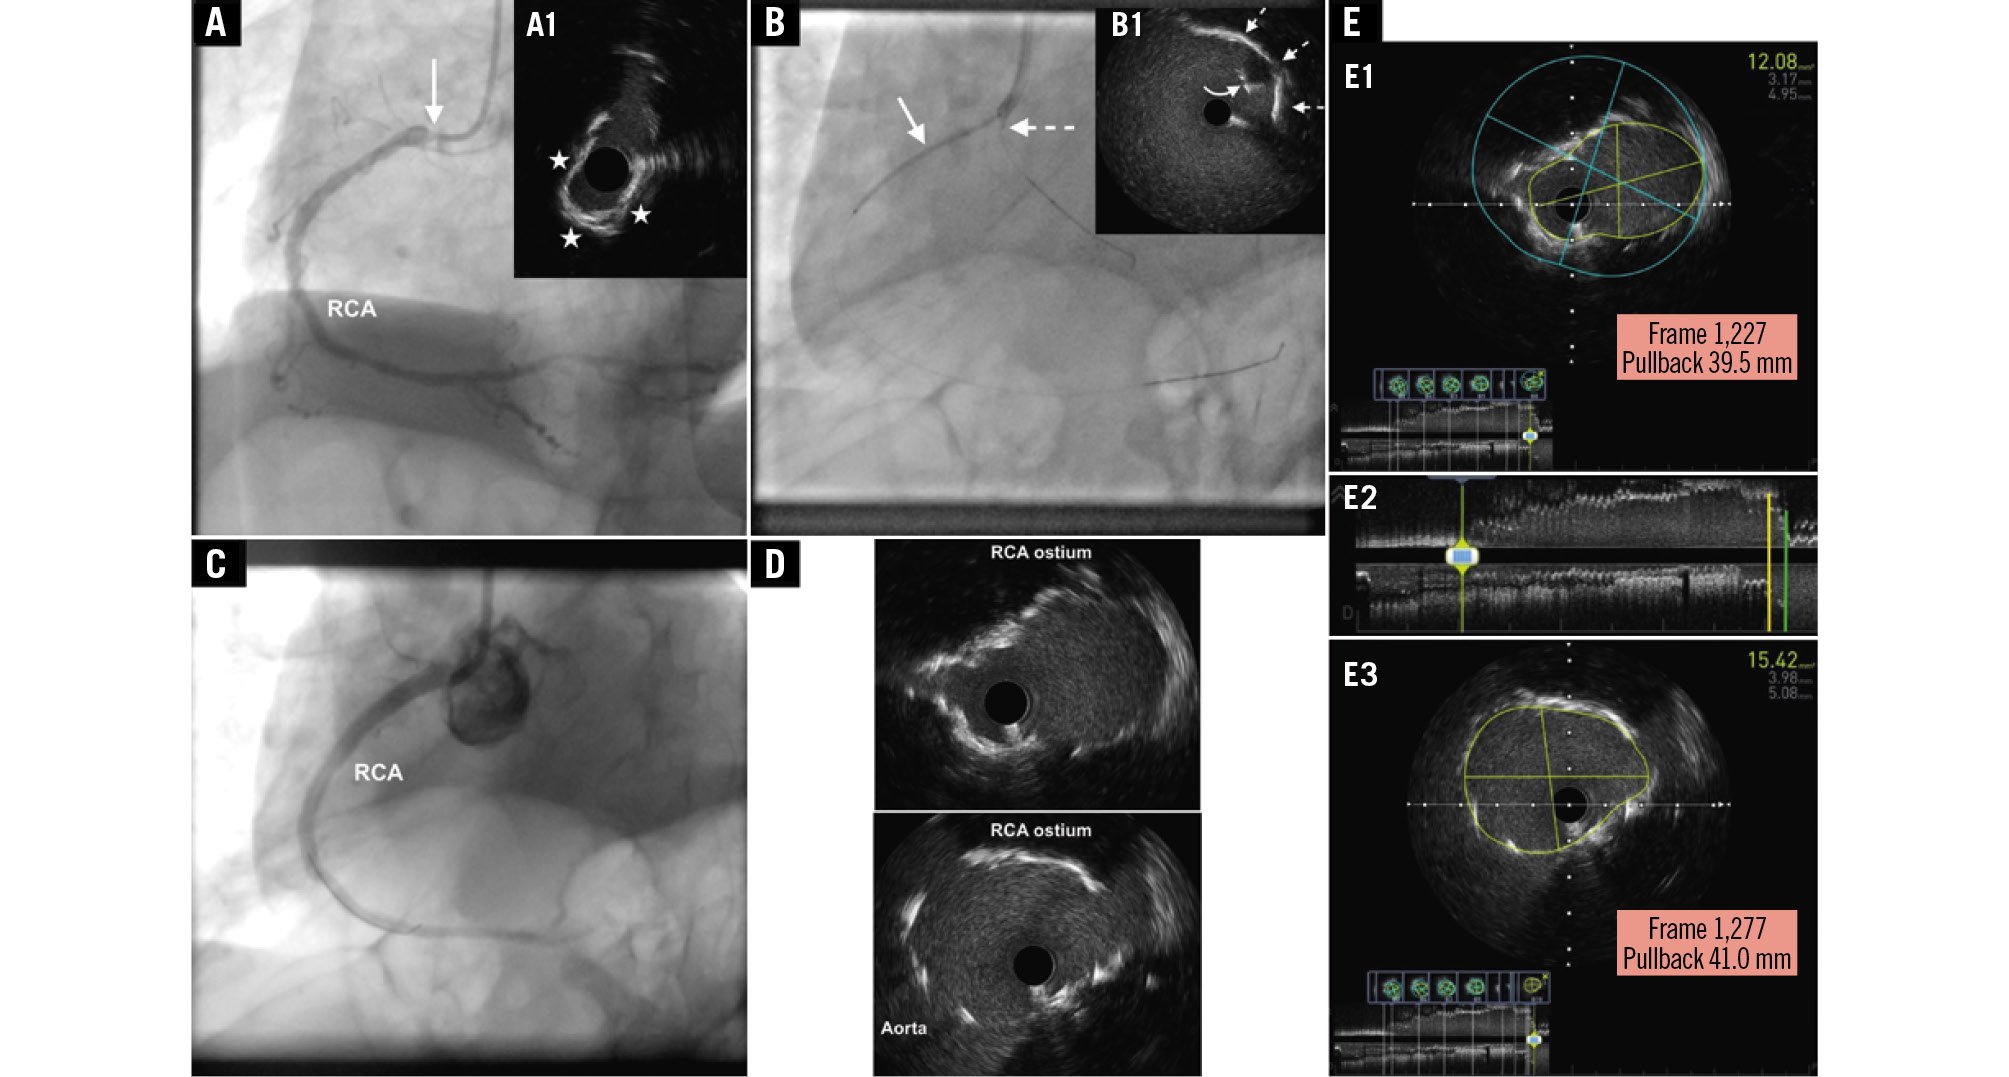

An 80-year-old male patient with type II diabetes mellitus and chronic kidney disease (CKD; baseline creatinine 2.16 mg/dL; estimated glomerular filtration rate 20 ml/min/1.73 m2) presented with non-ST-segment elevation myocardial infarction. He was referred for staged percutaneous coronary intervention (PCI) of a right coronary artery (RCA) aorto-ostial lesion (AOL) (Figure 1A, Moving image 1) following PCI of a culprit lesion in the left anterior descending artery (LAD). Echocardiography showed a left ventricular ejection fraction of 40% and hypokinesia of the LAD-dependent myocardium. We proceeded to perform a sheathless transradial PCI using a 7 Fr standard Judkins right 4.0 guide catheter with contrast-preserving techniques. Using the aortic calcification noted adjacent to the RCA ostium as a pointer, we confirmed proper ostial positioning of the catheter with electrocardiographic repolarisation changes after an injection of saline. The previous angiogram was used as a guide for wiring the RCA. Intravascular ultrasound (IVUS) was then performed showing a calcified AOL (Figure 1A). The lesion was dilated with a 3.5 mm scoring balloon and a 3.75 mm non-compliant balloon, and both balloons expanded fully and uniformly at 20 atm. A second (“floating”) guidewire was then placed in the aortic root followed by the positioning of a 3.5 mm x 34 mm drug-eluting stent across the lesion. An IVUS catheter was then advanced over the “floating” guidewire (Figure 1B), allowing us to adjust the stent position under live IVUS imaging so as to fully cover the ostium. The stent was then deployed and postdilated with a 4.0 mm non-compliant balloon inflated at 20 atm. Additional post-dilation of the stent covering the ostium and stent flaring was performed using a 4.5 mm non-compliant balloon inflated at 20 atm. An optimal PCI result was documented by IVUS and a single angiographic image using 3 ml of contrast medium (Figure 1C-Figure 1D–Figure 1E, Moving image 2, Moving image 3). Percutaneous coronary intervention of RCA AOLs still poses unique challenges and is associated with subsequent target lesion revascularisation (TLR) even when performed using new-generation drug-eluting stents1. Several anatomical reasons associated with a high risk of in-stent restenosis (ISR) are known to be prevalent in AOLs, such as fibrosis, calcification and thick muscular elastic tissue, all resulting in poor lesion distensibility and propensity for recoil. Further to these anatomical reasons, inaccurate stent placement, also known as geographical miss, has been associated with a threefold increase in ISR and TLR rates23. Geographical miss is diagnosed when any part of the circumference of the proximal stent edge is located proximal or distal to the aorto-ostial landing zone that is located within 1 mm proximal and distal to the aorto-ostial plane34. Furthermore, current practical recommendations advocate that stents in AOLs be deployed with 1-2 mm protruding into the aorta to ensure ostial coverage and to not hinder re-engagement of the vessel during future PCI5. Indeed, angiography-guided PCI of AOLs has been associated with 54% and 87% incidences of geographical miss detected by angiography and computed tomography angiography, respectively, partly because conventional angiography is inherently limited in accurately demarcating the true coronary ostium34. Furthermore, angiography-guided PCI of ostial lesions has been shown to be independently associated with use of a higher volume of contrast medium, that may potentially be particularly detrimental in patients at risk of contrast-induced nephropathy (CIN)6. Indeed, the risk of CIN in patients with severe CKD is high (26.6%) entailing an increased risk of adverse outcomes, including in-hospital death (9.6%)7. Consequently, the application of contrast-preserving techniques that would also ensure optimal stent positioning was imperative in our case. The “floating” IVUS technique herewith presented facilitated accurate aorto-ostial RCA stent positioning under the direct guidance of live imaging, therefore obviating the use of contrast medium, and potentially thereby helping to decrease the risk of TLR while simultaneously averting CIN and the associated increased morbidity and mortality. The successful application of this technique requires positioning the IVUS catheter in such a way as to clearly visualise the coronary artery ostium, followed by a slow and steady retraction of the stent towards the aorto-ostium until the proximal edge of the stent, recognised as a spherical echogenic structure with an acoustic shadow behind it, is visualised in the aorta immediately past the coronary artery ostium. Having the stent deployed in this position ensures complete stent coverage of the aorto-ostium, without excessive stent overhang into the aorta. Indeed, the application of this technique in our case resulted in an optimal stent location with the stent completely covering the aorto-ostium and having a part of the circumference of its proximal edge protruding about 1.5 mm into the aorta (Figure 1E), which is very much acceptable from a practical standpoint.

Figure 1. Conventional angiographic and IVUS images presenting the “floating” IVUS technique applied in the treatment of an aorto-ostial RCA lesion. A) Conventional angiographic image of the RCA at baseline (left anterior oblique 30° projection) depicting a high-grade ostial stenosis (arrow). Cross-sectional IVUS (60 MHz OptiCross catheter [Boston Scientific]) image (A1) depicting a severely narrowed ostium (minimal lumen area 3.5 mm2) due to a calcified lesion (calcium arc denoted by the asterisks). B) The stent is shown in position across the lesion (arrow). An IVUS catheter placed over a “floating” guidewire in the aortic root is also shown in such a position so that the transducer (dashed arrow) faces the ostium of the RCA. Cross-sectional IVUS image (B1) depicting the proximal edge of the stent (curved arrow) at the ostium of the RCA (dashed arrows), recognisable by its echogenic appearance with an acoustic shadow behind it, as opposed to a reverberation artefact, comprising arc-shaped, high-echoic lines appearing behind the proximal portion of the wrapped balloon and the balloon marker. C) Conventional angiographic image (left anterior oblique 30° projection) acquired at 30 frames per second depicting a good result after stenting the RCA lesion. D) Cross-sectional IVUS images from the RCA depicting optimal coverage of the ostium where the minimal stent area ranged between 12.0 mm2 and 15.0 mm2. E) Longitudinal view of the final IVUS recording (E2) showing complete stent coverage of the aorto-ostium (E1, corresponding to the cross-section marked with a yellow line in the longitudinal view) and a partially protruding stent (E3, corresponding to the cross-section marked with a green line in the longitudinal view) with a length of 1.5 mm (IVUS pullback speed: 1 mm/sec; frame rate: 30 frames/sec; see frame number and distance shown within the red rectangles in E1 and E3). IVUS: intravascular ultrasound; RCA: right coronary artery